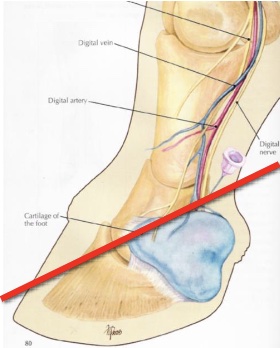

what is diagnostic perineural anesthesia

nerve block

what are the 4 types of nerve blocks

palmar/plantar digital

abaxial sesamoid

low 4-point

high 4-point

what is desensitized in a palmar/plantar nerve block

palmar/plantar 2/3 of foot

entire sole, navicular structures, distal interphalangeal joint, distal DDFT, distal sesamoidean ligaments